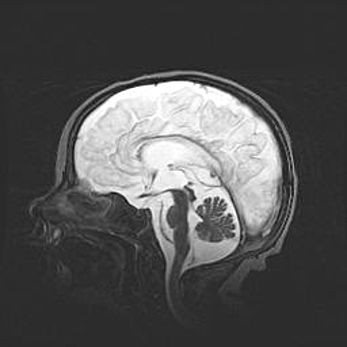

Аномалия Денди-Уокера. Признаки гипоплазии мозолистого тела.

Возраст: 5 месяцев 3 дня

Вес: 5550 г

Пол: мужской

Окружность головы: 39 см

Срок гестации: 40 недель

Аномалия Денди-Уокера – это порок развития головного мозга, для которого характерна триада симптомов: гипотрофия или аплазия червя мозжечка и/или полушарий мозжечка, расширение четвёртого желудочка с формированием ликворной кисты задней черепной ямки, гипертензионная гидроцефалия различной степени.

Гипоплазия мозолистого тела относится к дефектам внутриутробного этапа развития мозговой ткани, возникающим в процессе закладки структур головного мозга, что происходит на начальных этапах развития эмбриона.